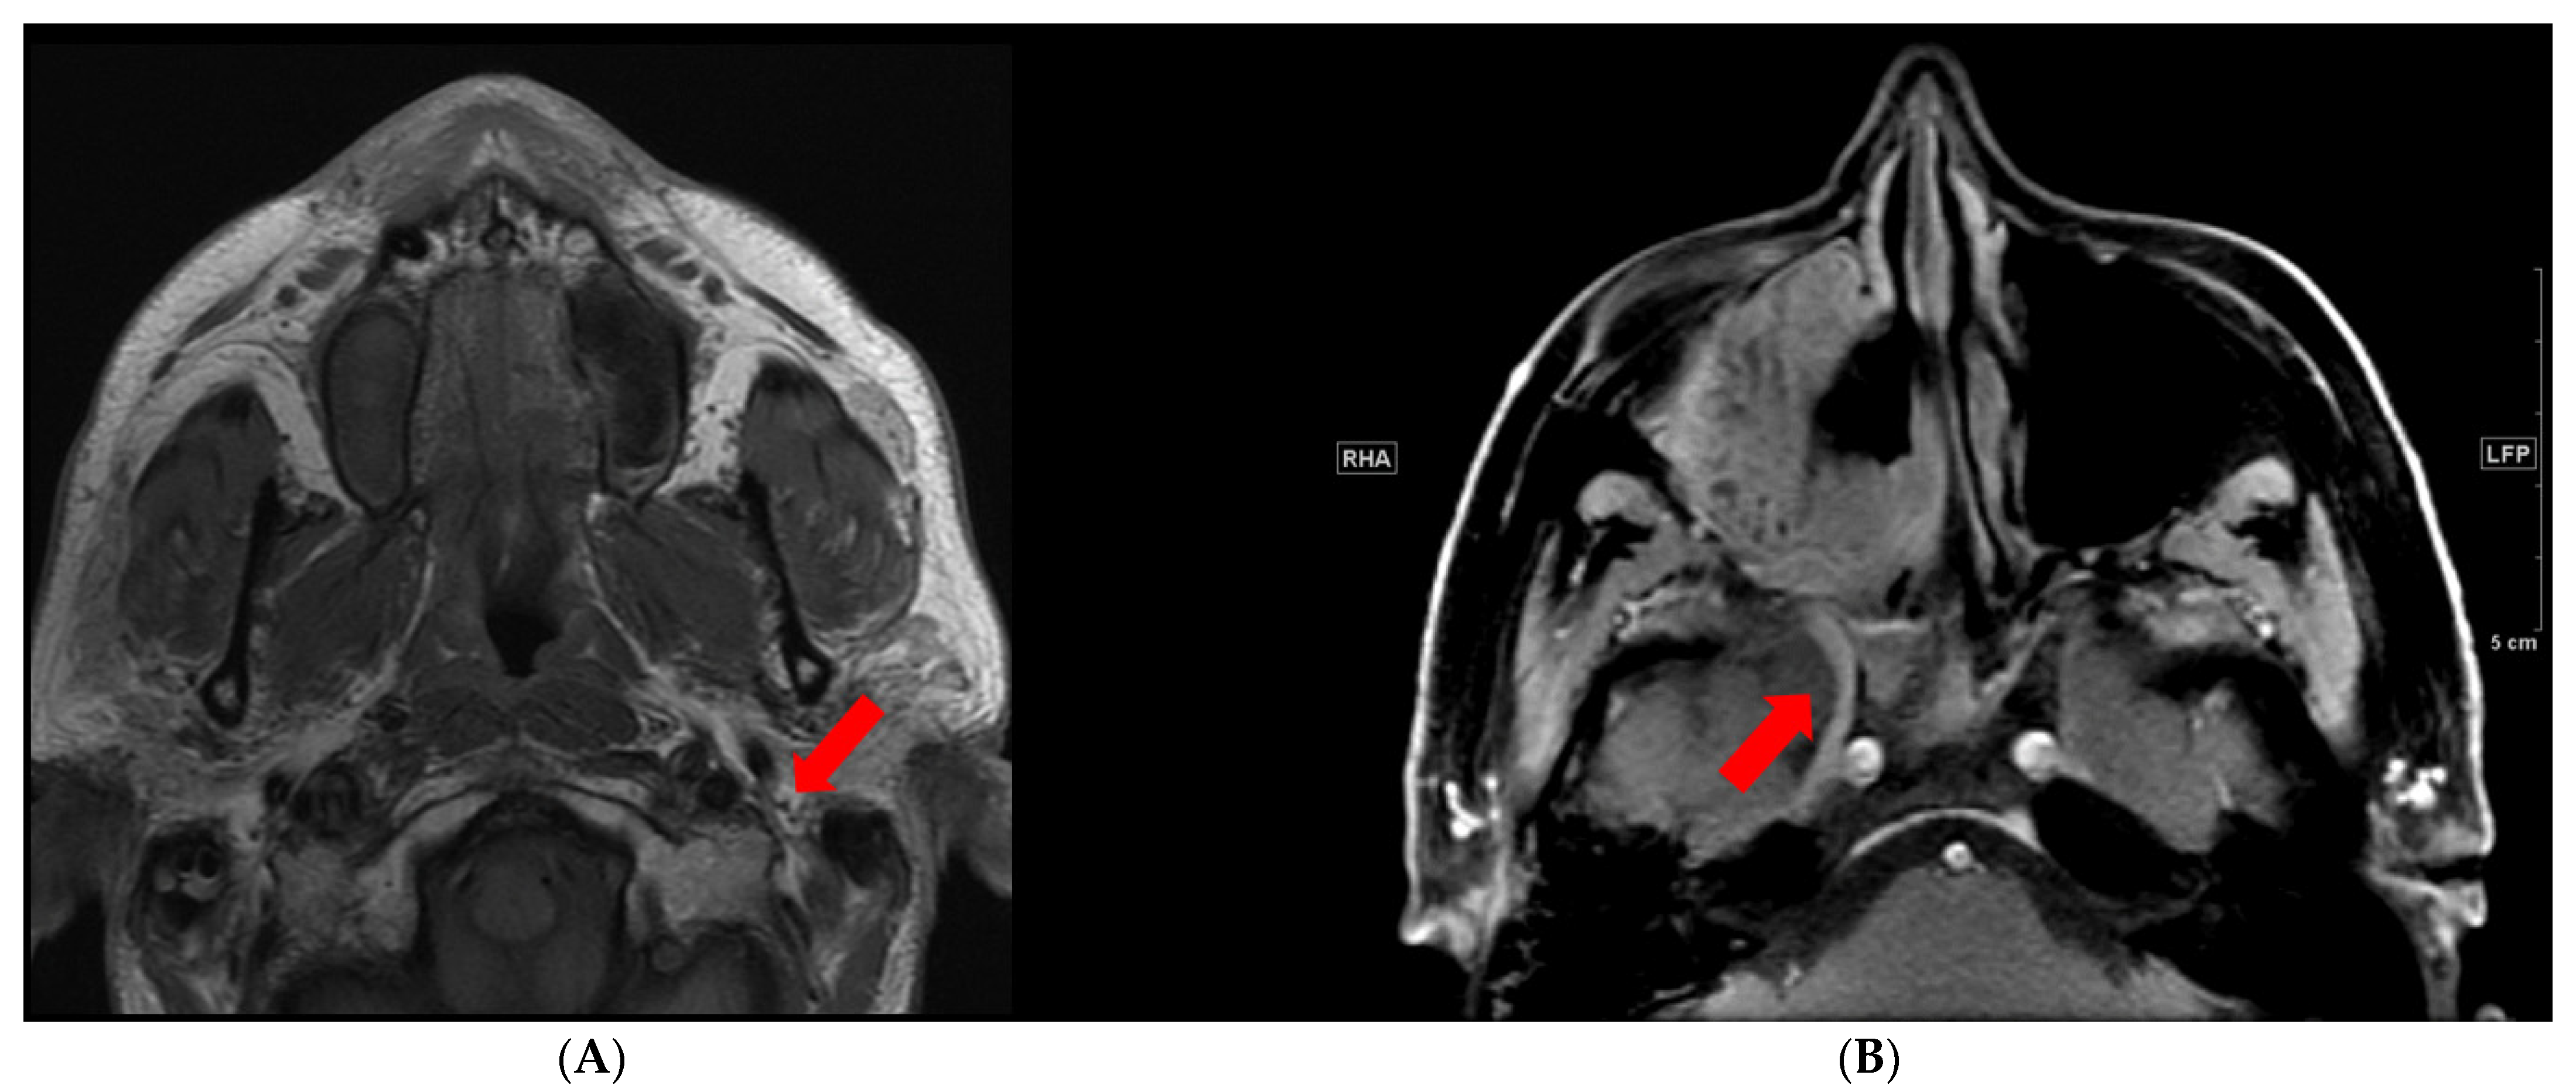

There are certain imaging sequences that are particularly important for PNTS evaluation. T1-weighted pre-contrast images without fat saturation are useful to look for the loss of T1 hyperintense fat that accompanies the T1 hypointense nerves (Figure 1A). This sequence is particularly crucial for evaluation of extracranial cranial nerves [8,9]. Postcontrast T1 should be accompanied by fat suppression. Fat suppression accentuates the abnormal nerve enhancement by eliminating intrinsically bright T1 fat signal that surrounds the nerve (Figure 1B). T2 sequences are important in assessing for edema; this sequence should also have fat suppression to visualize abnormalities.

Figure 1.

PNTS as seen on MRI. (A) Normal T1 hyperintense triangular fat around the facial nerve (arrow). (B) Postcontrast fat suppressed T1 image shows abnormally enhancing right V2 (arrow) and the pterygopalatine fossa.